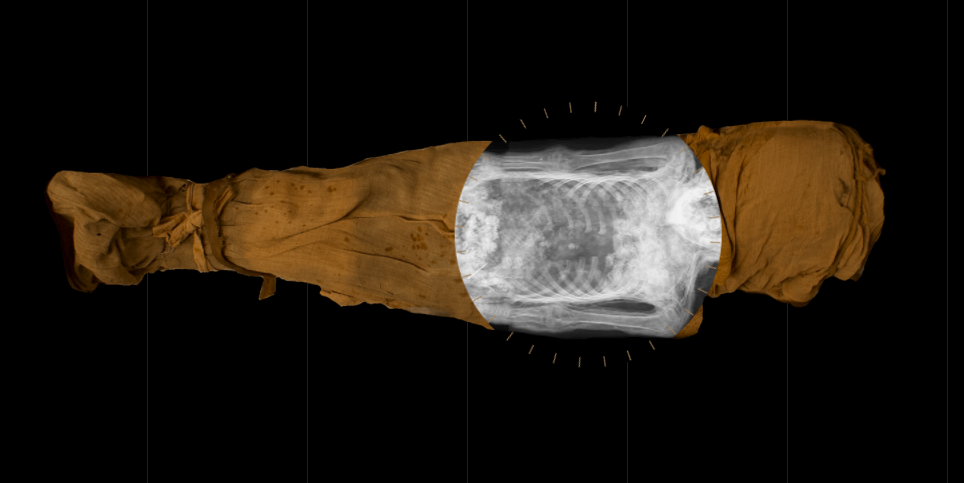

Image of the mysterious lady of the National Museum in WarsawWarsaw Mummy Project

But computer tomography conducted in 2016 suggested the mummy might be female, revealing a delicate bone structure, long hair, and mummified breasts.